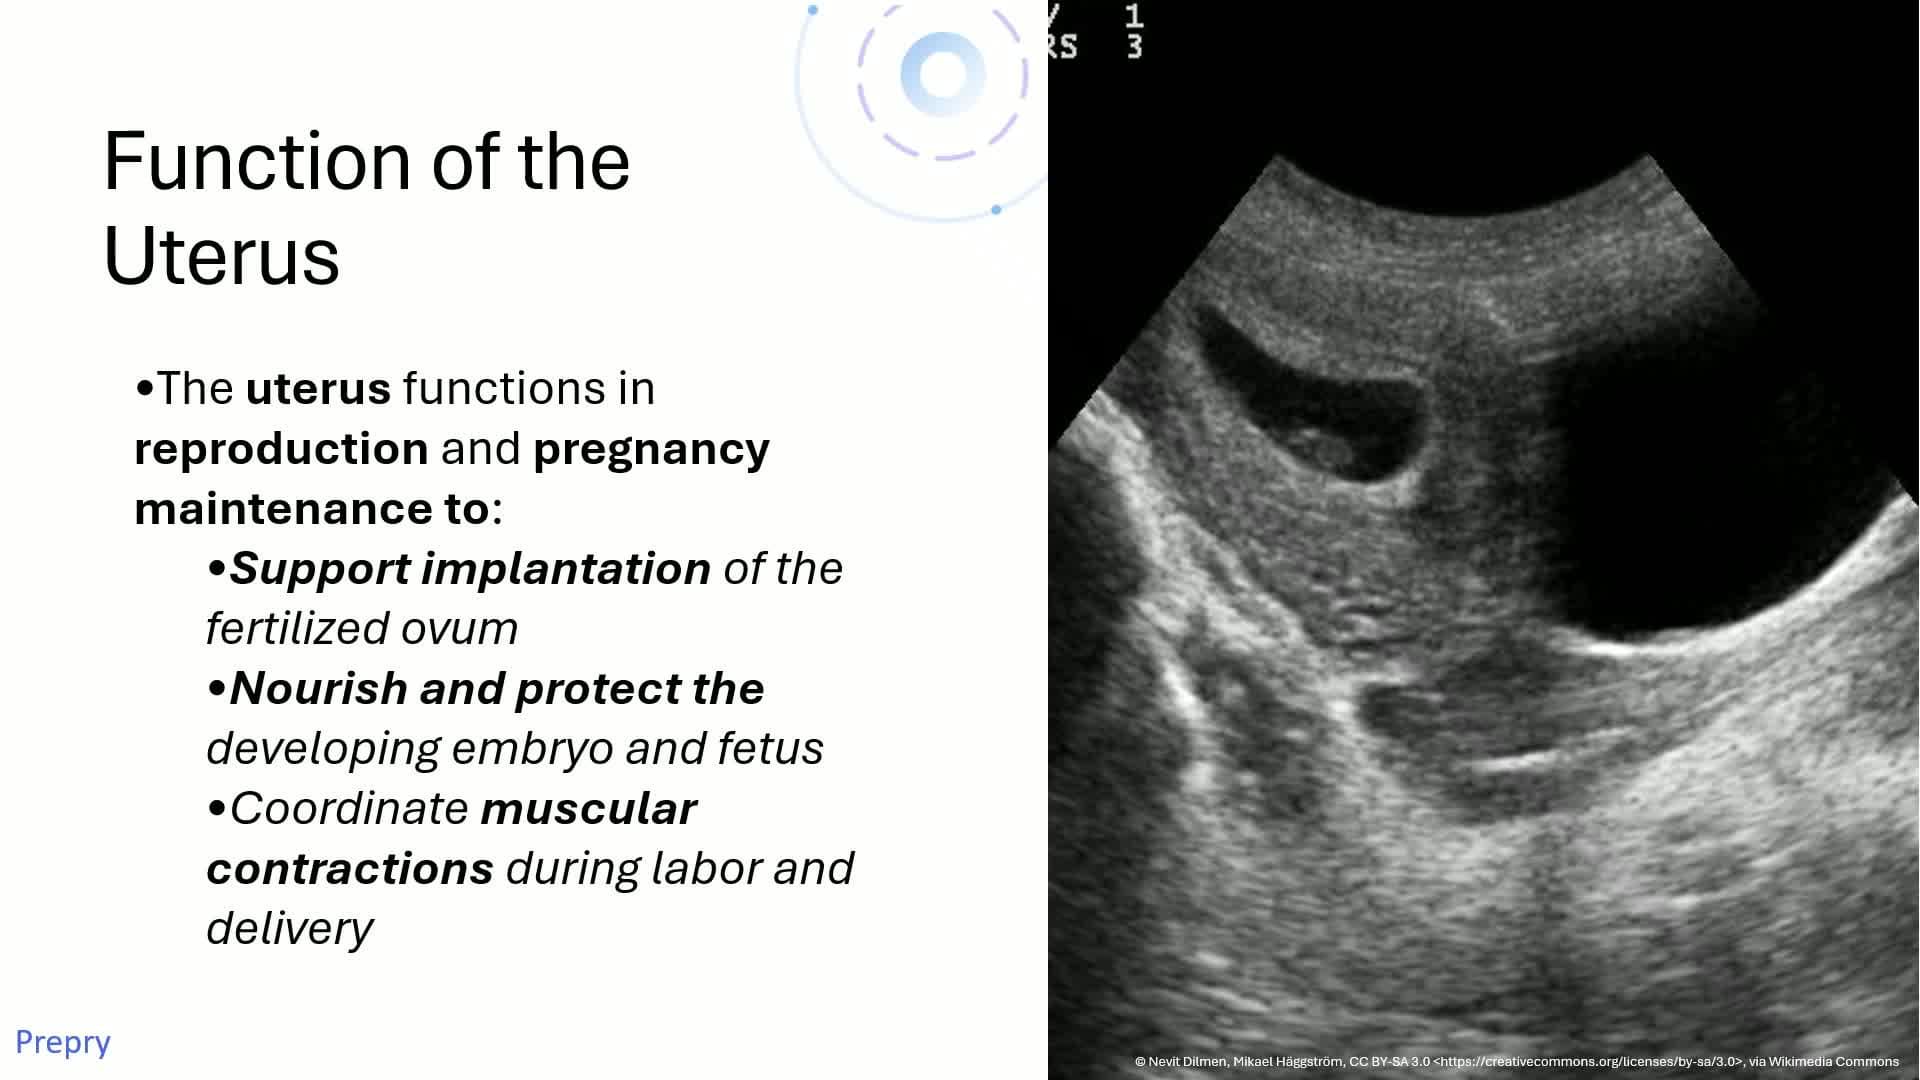

Unit 2.1 Uterine Anatomy

Unit 2.2 Uterine Anatomy